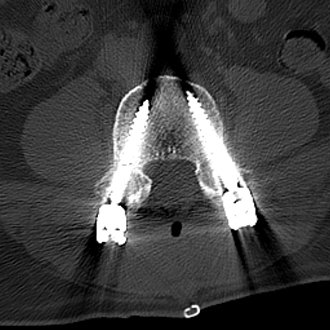

▲术中椎弓根螺钉精准置入

▲术后复查X线、CT